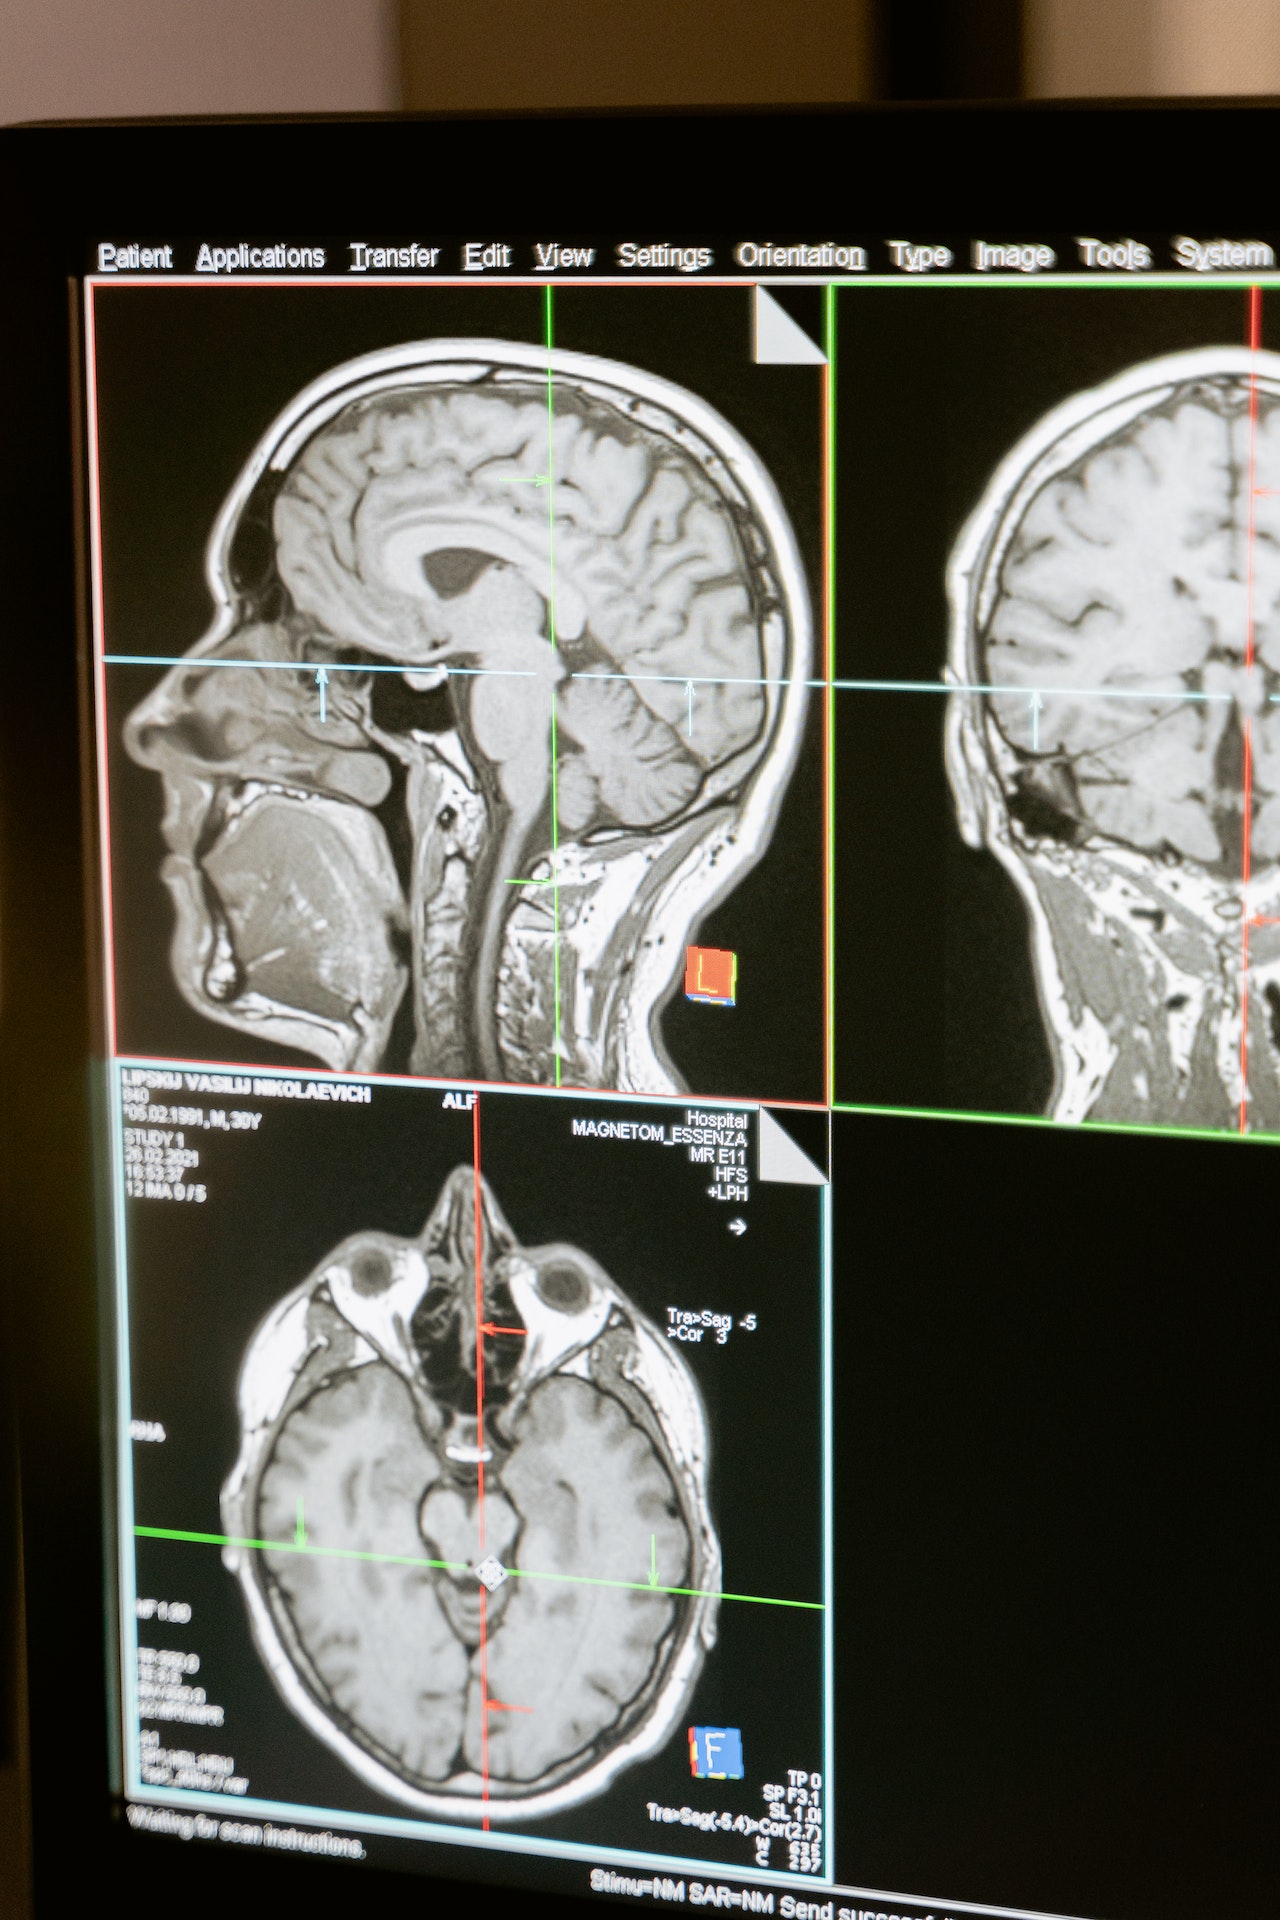

- יש לאתר את כל המסמכים הרלוונטיים לטיפול: מסמכי קופ"ח, תיק חדר מיון, דו"ח ניתוח, תיק אשפוז, תיק מרפאות חוץ, מכון רנטגן וכד';